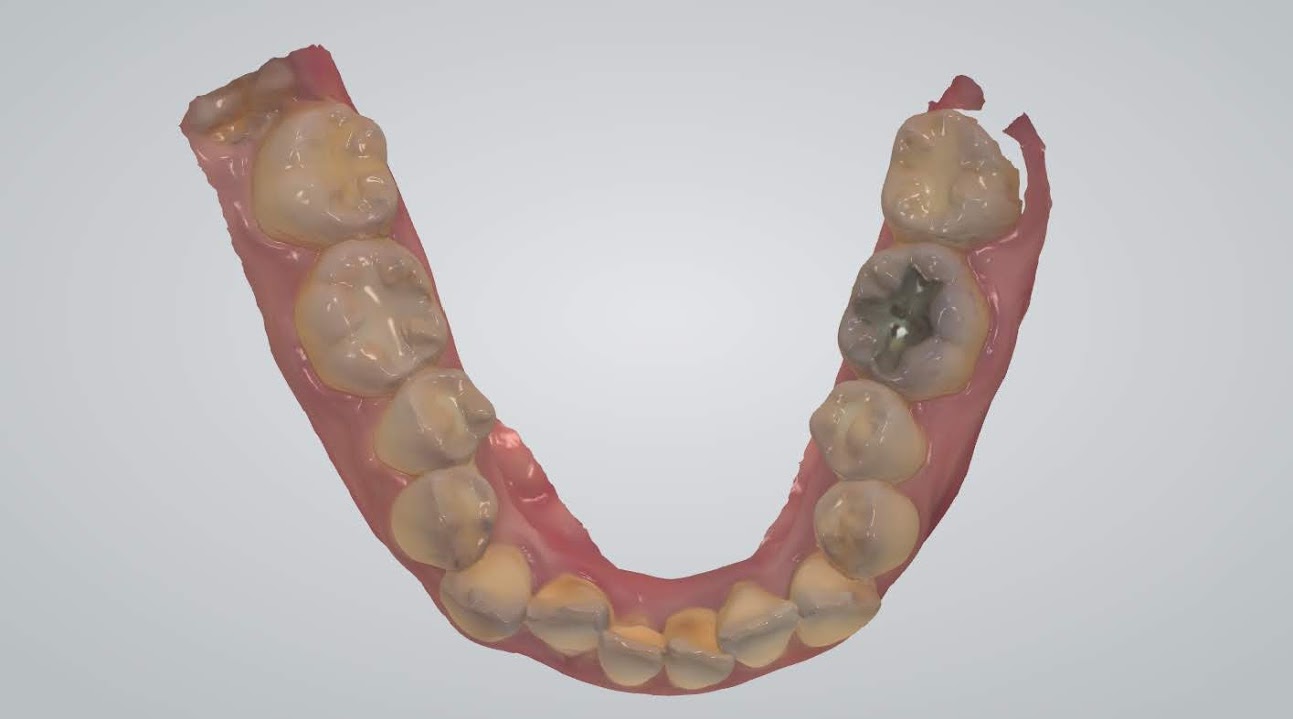

另外讓秤秤驚艷的先進設備還有這個-數位口腔掃描

能讓你清楚的看到每顆牙齒的長相、咬合狀況等,甚至連蛀牙、牙結石都照的很清楚,這樣當醫師在說明你的口腔狀況時,才能夠更了解且更快進入狀況

咬合狀況,因為有點亂直接拉黑,以免嚇到大家...

一直以來都覺得自己是滿口爛牙,再聽了醫生講解和看了自己的X光片、口腔掃描照後更加確定了~